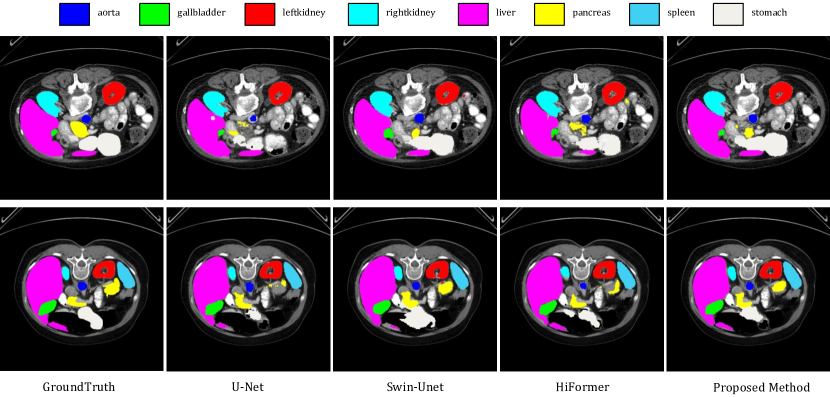

IV-C Quantitative and Qualitative Results

Table 1 showcases a comparative analysis of our proposed approach against several benchmarking methods. This includes both our preliminary models (baselines) and a few top-performing, state-of-the-art architectures.

For a comprehensive understanding of our method’s effectiveness, we evaluated three distinct baselines:

Baseline: This model forms the foundation of our approach and excludes the enhancements of dual attention and ISIM. Instead, it only employs an efficient attention module in each transformer block.

Proposed Method (without ISIM): An evolution of the initial model, this version incorporates both channel and spatial attention. As we describe it, this combines the efficiencies of both attention mechanisms.

Proposed Method: This embodies our holistic approach, utilizing all features, including ISIM.

Sequential enhancements in our model evidently enhanced its performance. Incorporating dual attention and subsequently, the ISIM, empirically validated our strategy’s potency in addressing medical image segmentation challenges.

In this thorough comparison with top-tier models, our methodology underscores its superiority. To emphasize, the Dice Similarity Coefficient (DSC) of our proposal impressively settles at 82.16%, outclassing formidable contenders like the HiFormer, which rests at 80.39%.

A salient feature of our model is its aptitude for delineating finer anatomical structures. The integration of ISIM markedly amplifies this capability. This prowess is evident in the Gallbladder’s segmentation, where our technique delivers a 71.48% score, overtaking others like the TransDeepLab’s 69.16%. Similarly, the Pancreas, a traditionally intricate organ to segment due to its size, witnesses a conspicuous uplift with our method, achieving 65.02%, surpassing even the FFUNet-trans’s 64.17%.

In the segmentation of more pronounced organs, our model remains unparalleled. The Kidney (L) and Kidney (R) respectively logged scores of 85.45% and 80.85%. Noteworthy is the Liver’s segmentation, where our approach, with a score of 94.85%, nearly mirrors the HiFormer’s 94.61%. Furthermore, in segmenting the Spleen, our model, at 91.62%, slightly edges out our own baseline, which clocked 91.05%.